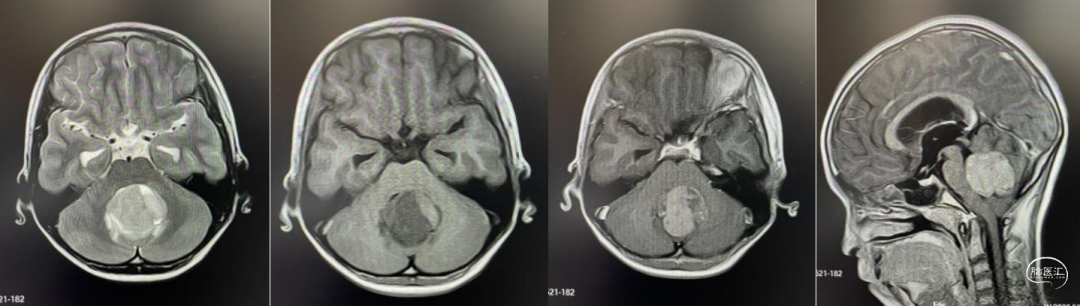

头部MRI显示:小脑蚓部可见一团块样等T1、等-长T2信号灶,边缘模糊,大小约3.5*3.6cm,增强后病灶明显强化,第四脑室明显受压,慕上脑室轻度扩张,中线结构居中。